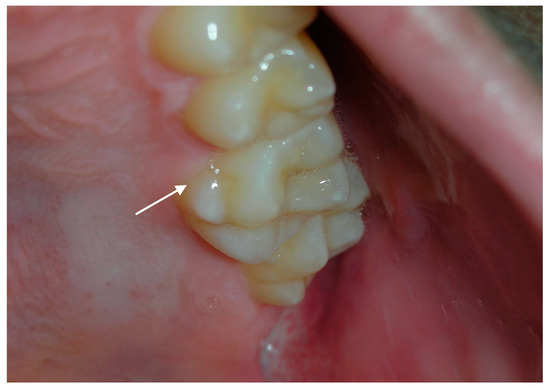

- Neurofibromas

| Oral/perioral Neurofibromas | Presence of nodules was evaluated by palpation and examination of soft tissues | |||||

| Neurofibroma | 4% | 0 | 0.0043 |